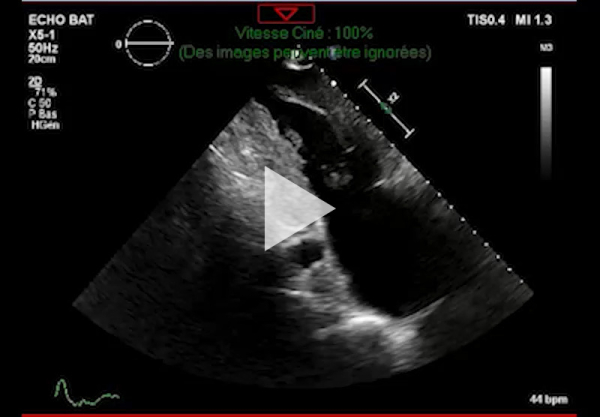

Vidéo 1 - Échocardiographie 2D en incidence parasternale grand axe

Figure 2 : Échocardiographie 2D Coupe parasternale petit axe (mesure des parois VG)

- Ventricule gauche non dilaté, hypertrophie concentrique symétrique majeure non-obstructive, hypokinésie globale, aspect scintillant du myocarde

- FEVG 45- 50 %

- Pressions de remplissage VG probablement élevées

- Dilatation bi-atriale marquée (OG 54 ml/m²)

- Fuite mitrale centrale modérée, épaississement des valves

- Ventricule droit non dilaté modérément hypertrophique

- Fonction systolique VD diminuée

- Hypertension pulmonaire peu probable (Vmax IT 2,85 m/s)

- Décollement péricardique minime inférieur